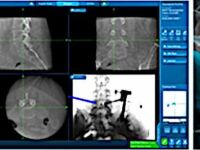

Виды медико-хирургической помощи